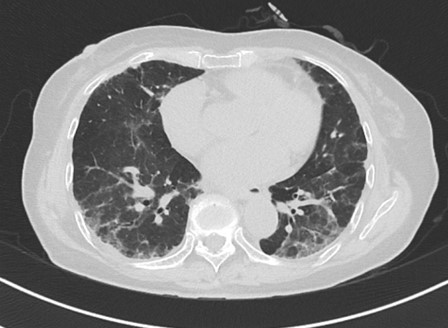

動(dòng)植物蛋白是過敏原之一,我們比較熟悉的是飼鳥肺、鴿子肺,這類鳥類蛋白通過鳥類的排泄物、血液或者羽毛致病。還有一些特殊的職業(yè),如咖啡工人(來源:咖啡豆粉塵)、大豆工人(來源:大豆殼),從事牡蠣殼加工的工人(致病物質(zhì):軟體動(dòng)物殼蛋白;軟體動(dòng)物殼粉塵)都有可能出現(xiàn)過敏性肺炎。

微信圖片_20240805163630.png

微生物也會(huì)成為過敏原,在大棚中養(yǎng)殖蘑菇、在制糖廠處理甘蔗,或者在田地或大棚當(dāng)中種植谷物,木工、煙草生產(chǎn)線工人可能會(huì)遇到真菌菌屬;空調(diào)的過濾網(wǎng)或加濕器中可能會(huì)出現(xiàn)放線菌,從而導(dǎo)致加濕器肺或者空調(diào)肺。

此外,一些化學(xué)物質(zhì)也會(huì)成為過敏原,例如,接觸油漆、塑料的人,也就是接觸異氰酸酯或聚氨酯等化學(xué)物的人,也會(huì)導(dǎo)致過敏性肺炎的發(fā)生。